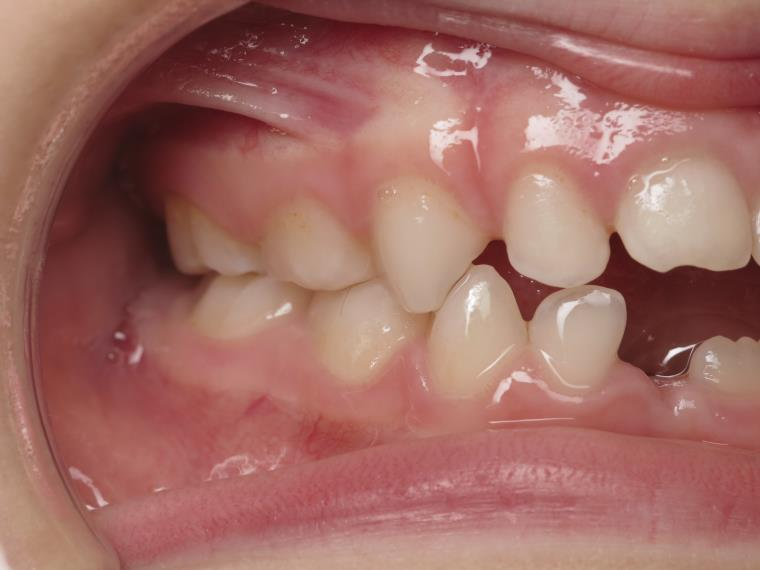

14 béance inversé gauche 5 ans

inversion postérieur coté droit et espace entre l'arcade du haut et du bas (béance)